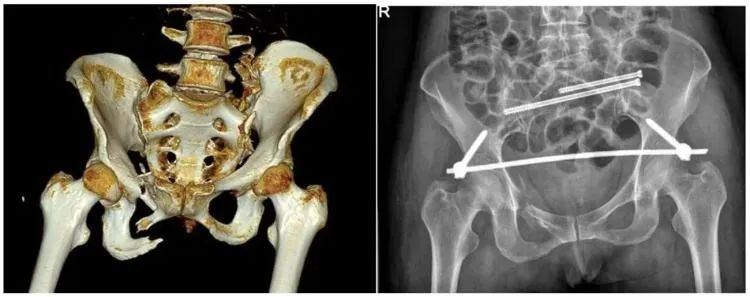

二、穩定性骨折&不穩定性骨折

另外,我們根據骨盆骨折是否穩定可以分為穩定性的骨折和不穩定性的骨折。如果是不穩定性的骨折醫生可能會建議病人進行手術治療,把不穩定性的骨折變成穩定性的骨折。

【醫療科普】:穩定性骨折影像

穩定性骨折

【醫療科普】:不穩定性骨折影像

不穩定性骨折